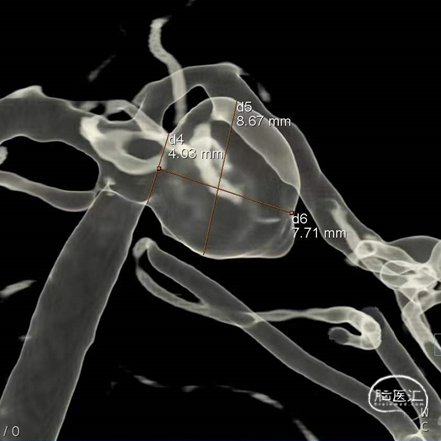

经测量可得动脉瘤宽度平均值为8.88mm,动脉瘤最小高度为7.71mm,瘤颈约为4.03mm。参考尺寸选择表,选择WEB™ SL 10*5,VIA™ 33微导管。